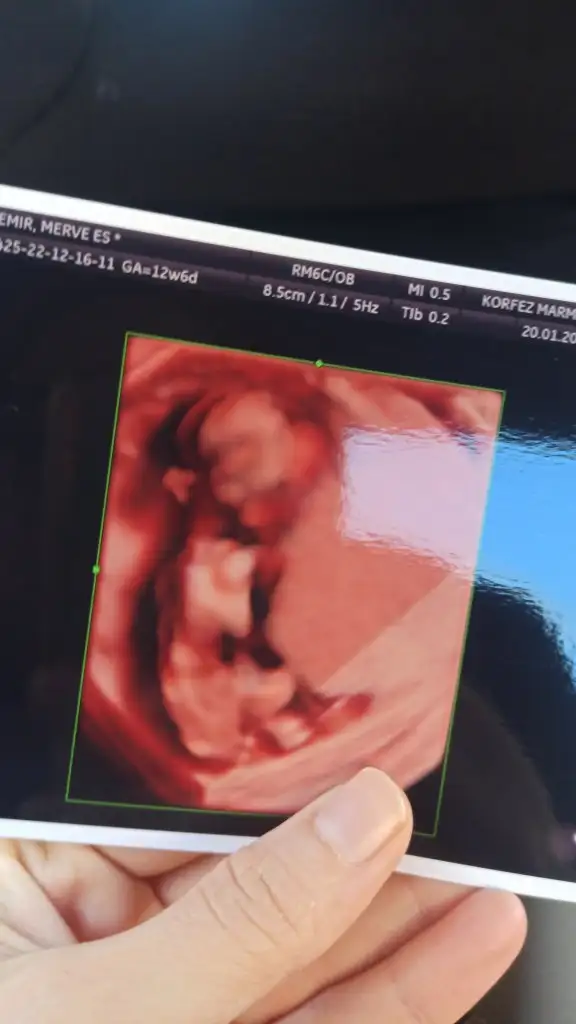

Bana da tahminde bulunur musunuz 12+6 haftalık . Siyah ultrasonda 11+6 haftalik karından ultrason 😊😊😊

• IMG-20230120-WA0011.webp

IMG-20230120-WA0011.webp

18,1 KB · Görüntüleme: 54